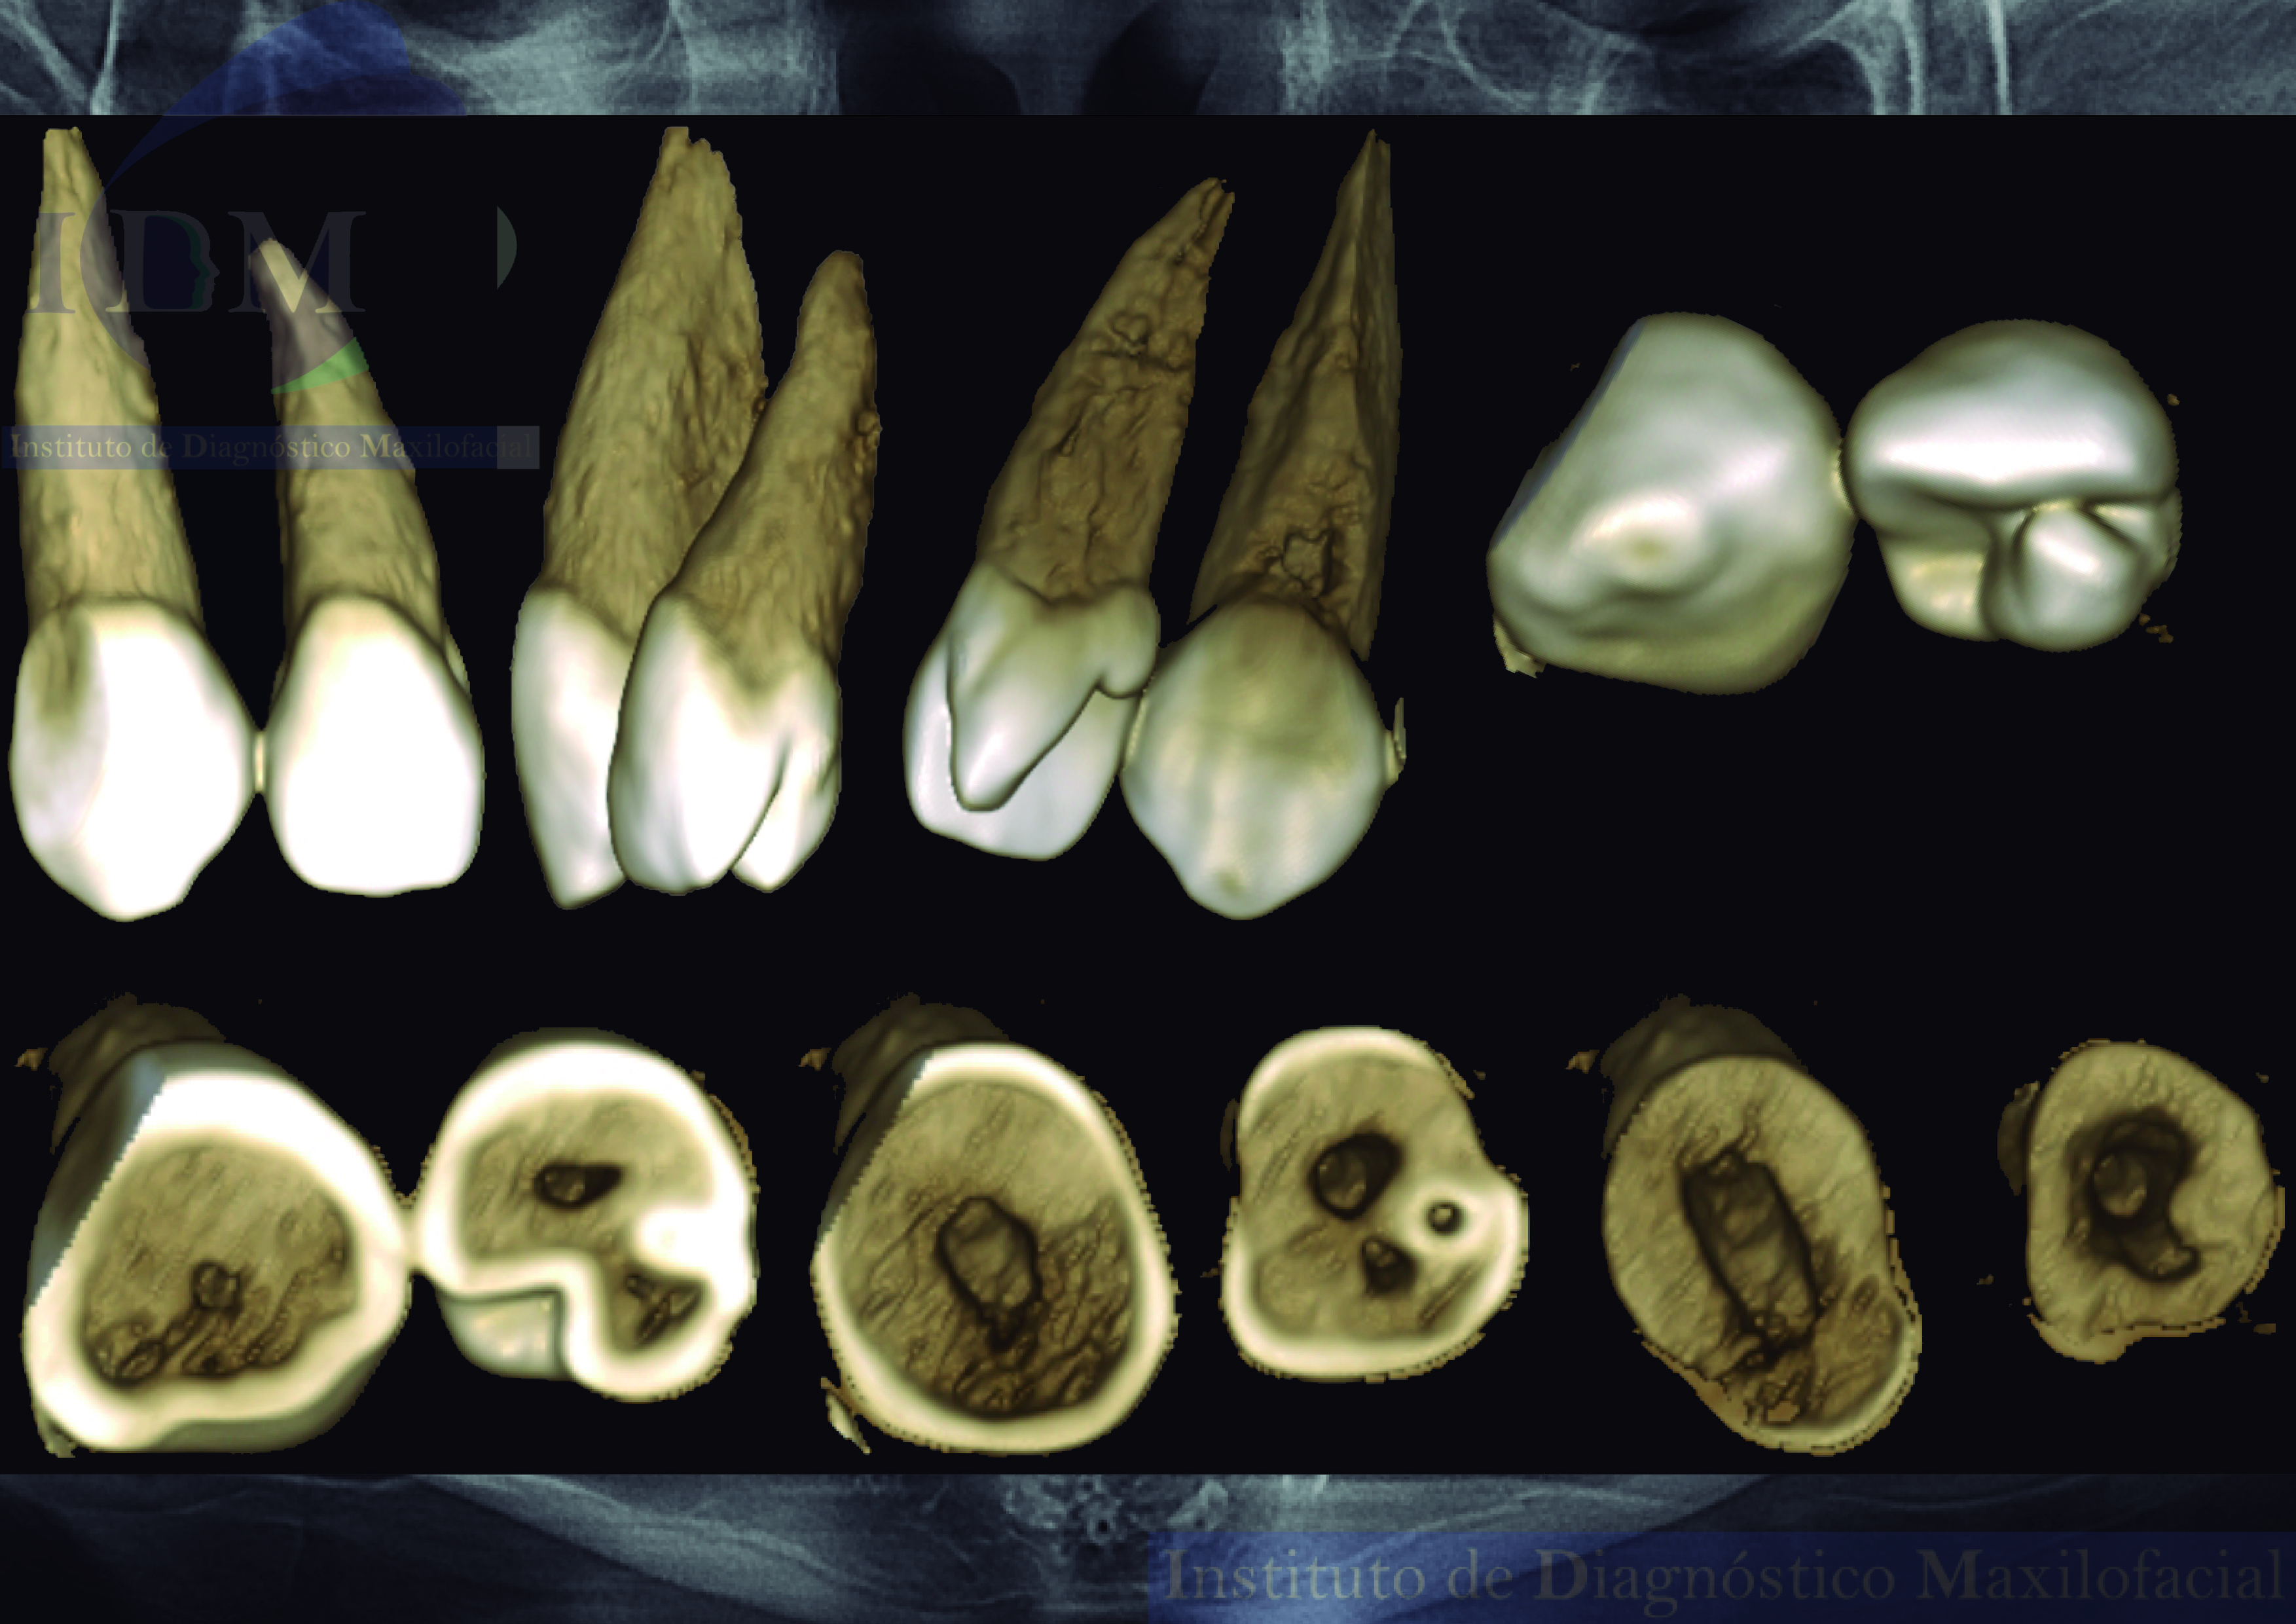

En las reconstrucciones 3D se representa la invaginación del esmalte con presencia de cúspide en talón (Figura 4).

RECONSTRUCCIÓN 3D

Conclusión: Alteración en la morfología coronaria compatible con Dens Invaginatus y cúspide en talón.

El presente caso, muestra alteración en la morfología coronaria compatible con dens invaginatus y cúspide en talón, con lo que se podrá determinar el mejor plan de tratamiento a seguir.